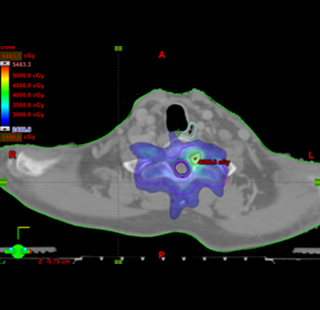

일반적인 방사선치료는 종양 및 주위 정상장기가 동일한 양의 방사선을 받게 되어 있어서 방사선에 취약한 정상조직이 종양 내부 또는 종양과 인접해 있으면 정상조직의 손상을 우려하여 암의 완치를 위한 고선량의 방사선을 조사할 수 없습니다. 세기조절방사선치료 (Intensity-Modulated Radiation Therapy; IMRT) 는 이러한 문제점을 해결 할 수 있는 같은 평면에서 조사 받는 방사선의 양을 서로 다르게 하여 정상조직은 보호하면서 종양에만 집중적으로 방사선을 조사 할 수 있습니다. 아래 그림과 같이 뼈에 전이된 종양을 치료하면서 치료 부위 내부에 있는 척수신경의 방사선손상을 피하고 싶을 때 이용할 수 있는 가장 이상적인 치료 방법입니다. 하지만 현재 의료보험 제도하에서는 폐암환자가 치료 전액은 부담해야하는 고비용 치료법이며, 폐암환자 모두에게 일반 방사선치료와 비교 시 탁월한 치료법은 아니므로 세기조절방사선치료의 선택은 담당의사와의 협의가 필요합니다.